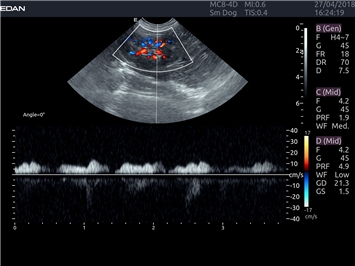

EDAN Acclarix LX4 VET представляет собой профессиональную ультразвуковую систему, специально разработанную для ветеринарных исследований. Сочетание стабильности, высокой производительности и эффективности делает эту систему идеальным выбором для современной ветеринарной практики.

Постоянно-волновой допплер:

Да

Импульсно-волновой допплер:

Триплексное сканирование:

Дуплексное сканирование: